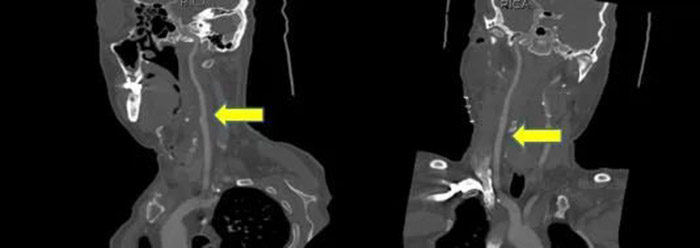

术前、术后TCD影像对比颅内大脑中动脉血流量明显上升